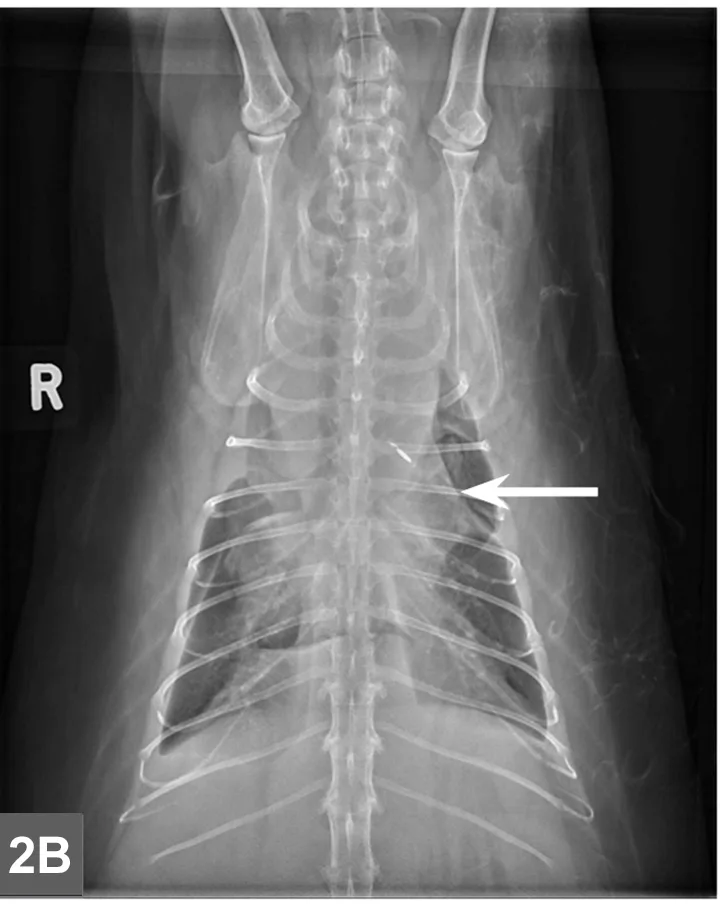

Featured Image

FIGURE 2B

Cranial mediastinal mass in a cat. There is also widening of the cranial mediastinum with rounded margins and border effacement of the cranial margin of the heart in the VD view. Pleural effusion contributes to effacement of the cardiac silhouette and to the widened appearance of the cranial mediastinum in the VD view (arrow).